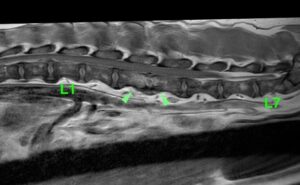

MRI検査で腰の背骨と椎間板に白い領域がみられ(黄緑矢頭)、炎症が疑われた。

さらにこの病変部は造影剤によって、より白く染まったことから椎間板脊椎炎が疑われる。